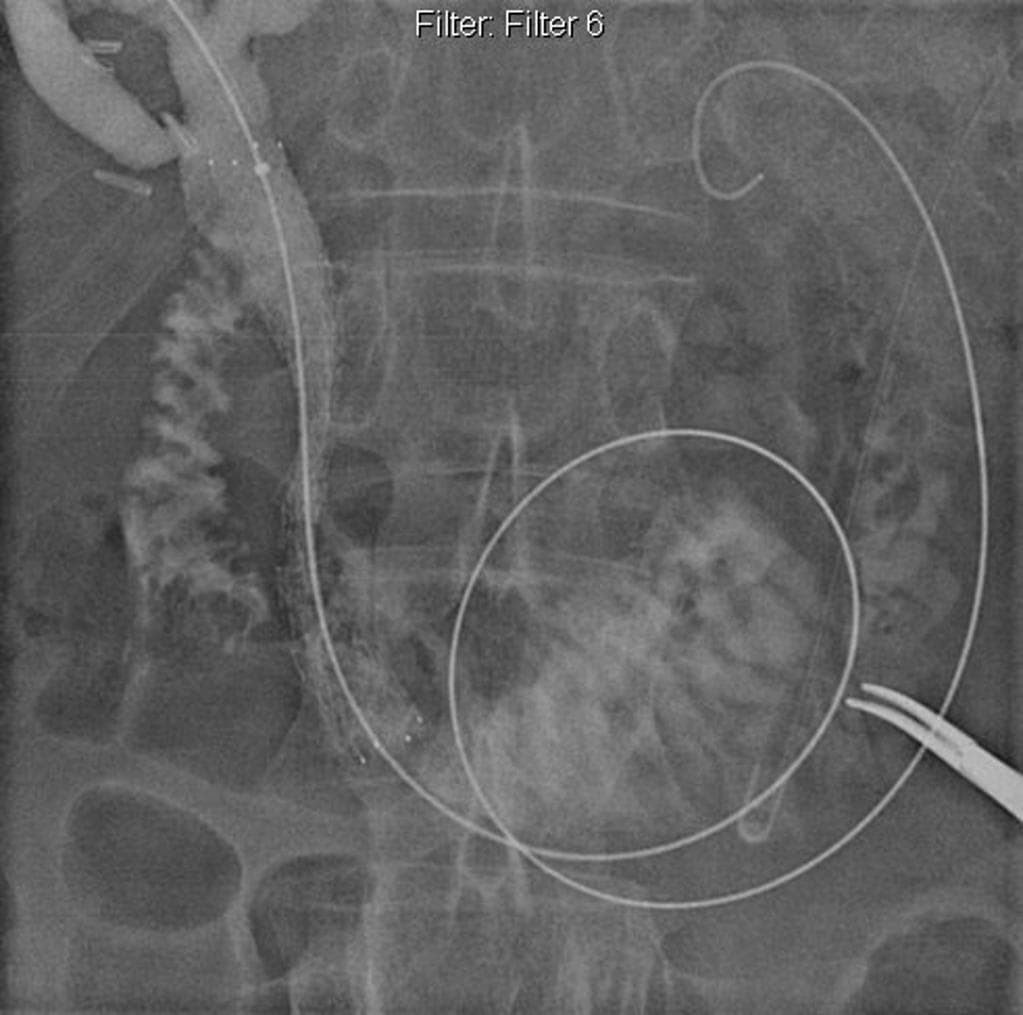

Series (9)

- Có giãn dạng thoi các ống mật ngoài gan (bao gồm ống mật chủ và ống gan chung) chứa nhiều ổ giảm tín hiệu trên mọi chuỗi xung, phân bố theo trọng lực, phù hợp với hình ảnh sỏi.

- Không có giãn đường mật trong gan.

Interpretation: U nang ống mật chủ (type 1) kèm theo tổn thương IPMN nhánh bên phát hiện tình cờ (incidental side branch IPMN).

U nang ống mật chủ - type I (choledochal cyst - type I)